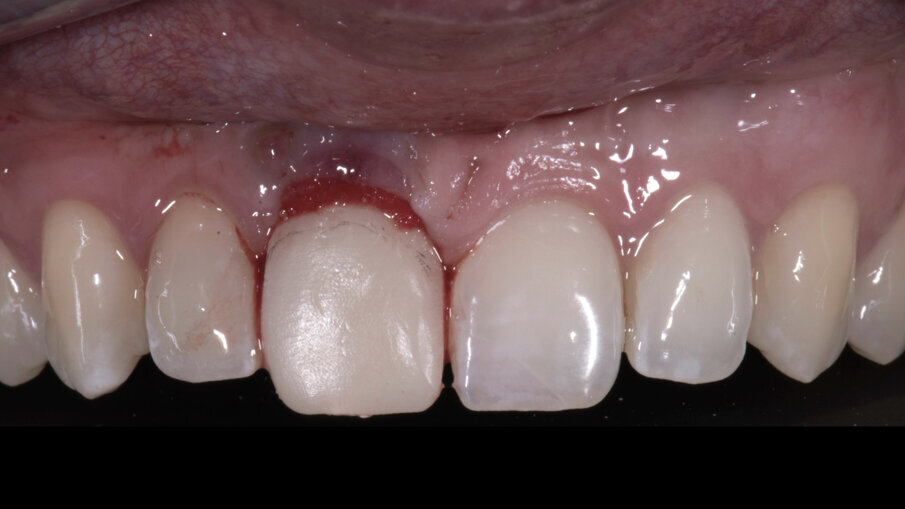

Trascorsi quattro mesi, ad avvenuta osteointegrazione dell’impianto, il condizionamento dei tessuti appariva ottimale sia in termini di qualità dei tessuti sia in termini di volume rigenerato. I profili gengivali erano perfettamente armonici e naturali grazie al provvisorio (Fig. 29). A questo punto, dopo avere svitato il provvisorio dall’impianto, ho copiato con lo scanner intra-orale la posizione delle papille e della parabola gengivale. In tal modo, creando la cosiddetta “Maschera gengivale”, ho condiviso con il software le informazioni morfologiche necessarie per realizzare i manufatti protesici definitivi (Figg. 30, 31).

Fig. 28_Guarigione dopo 4 mesi.

Fig. 29_Aspetto dei tessuti condizionati dopo la rimozione del provvisorio.